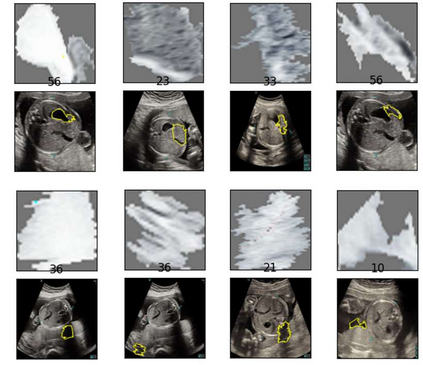

Although deep neural networks (DNN) have achieved state-of-the-art performance in various fields, some unexpected errors are often found in the neural network, which is very dangerous for some tasks requiring high reliability and high security. The non-transparency and unexplainably of Convolutional Neural Networks (CNN) still limit its application in many fields, such as medical care and finance. Despite current studies that have been committed to visualizing the decision process of DNN, most of these methods focus on the low level and do not take into account the prior knowledge of medicine. In this work, we propose an interpretable framework based on key medical concepts, enabling CNN to explain from the perspective of doctors' cognition. We propose an interpretable automatic recognition framework for the ultrasonic standard plane, which uses a concept-based graph convolutional neural network to construct the relationships between key medical concepts, to obtain an interpretation consistent with a doctor's cognition. Extensive experiments have empirically shown that our model can meaningfully explain the decision of the classifier and provide quantitative support.